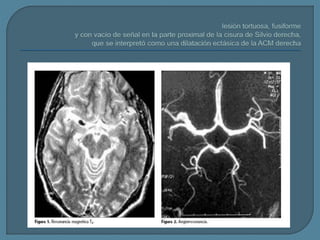

Este documento describe los aneurismas fusiformes, que afectan los vasos largos que no se ramifican y pueden ser agudos o crónicos. El principal signo diagnóstico es un segmento fusiforme largo o una dilatación arterial ovoidea. La tomografía computarizada y la resonancia magnética nuclear pueden usarse para identificar un vaso ectásico dilatado con señales de intensidad mixta. Los aneurismas fusiformes pueden ser ateroescleróticos o no ateroescleróticos.